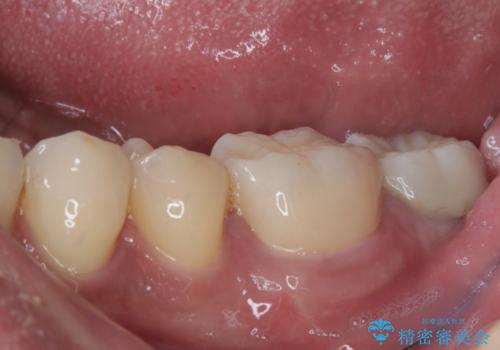

- 左下の歯が欠けてしまったとのことで来院された患者様です。

大きな銀歯が装着されており、その周りからむし歯が広がっている状態でした。

特に症状はなく、神経組織も健全な状態であったため、むし歯を全て取り切った後にフルジルコニアクラウンにて補綴することとしました。